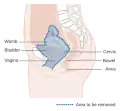

-

Diagram showing the area removed with a posterior surgery

Diagram showing the area removed with a posterior surgery -

Diagram showing the area removed with a total operation

Diagram showing the area removed with a total operation -

Diagram showing the area removed with an anterior operation

Diagram showing the area removed with an anterior operation